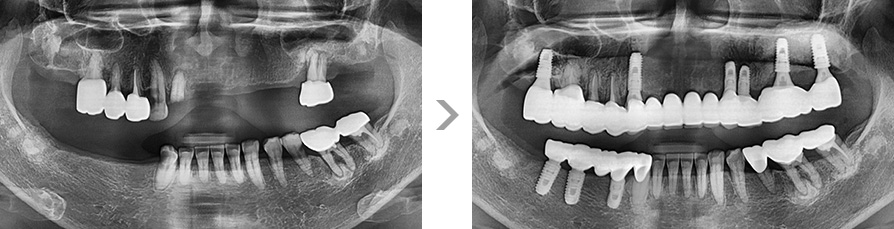

잇몸뼈가 녹아내려 임플란트 12개 식립 진단을 받고 내원하신 40대 여성 환자 분입니다.

뉴욕메디슨치과의 비수술 잇몸 치료를 통해 전치부 잇몸 건강이 개선되어 흔들리던 치아들이 자리를 잡았습니다.

또한 치조골이 손실된 곳에는 뼈이식술을 동반하여 임플란트 4개 식립만으로 치료를 마치실 수 있었습니다.

잇몸 염증으로 치조골 손실이 많은 상태

잇몸 건강이 회복된 앞니는 보존하고 임플란트 4개 식립